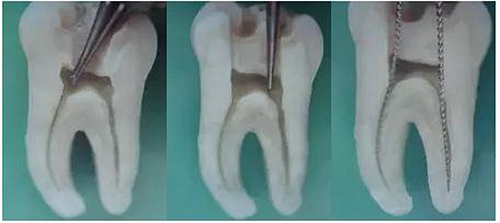

3、根管口的直線通道:特別對于彎曲根管!預(yù)備根管之前是否重視這個環(huán)節(jié),盡管找到了根管口,銼也能順利進(jìn)入根管,但根管口的直線通道是否建立也是衡量醫(yī)生操作技能的重要依據(jù)。

方法很多:手動器械操作時我們可以采用價格便宜的“GG”鉆,PROTAPER機(jī)動預(yù)備時可以采用SX銼。

圖7彎曲根管冠部處理之前 圖8用GG鉆或SX銼進(jìn)行預(yù)備

圖9處理后形成的直線通道

我的病例1_冠部處理成直線通道后的充填效果

我的病例2_下頜7"C"型根管的充填效果